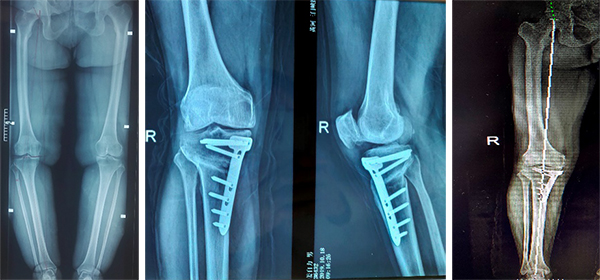

5、胫骨高位截骨术

自2007年开始采用胫骨高位截骨术治疗膝关节骨性关节炎,胫骨高位截骨术通过手术纠正了下肢异常的力线,恢复了下肢正常力线,有效地缓解了膝关节内侧间室的压力,有效治疗膝关节疼痛,延缓了膝关节内侧骨性关节炎的进一步发展,有利于内侧间室软骨再生,延长了膝关节使用寿命,甚至避免后期骨性关节炎明显加重而被迫行膝关节置换术,胫骨高位截骨术挽救了许多膝关节炎病人,取得了良好的临床疗效,获得了广大患者的一致好评。